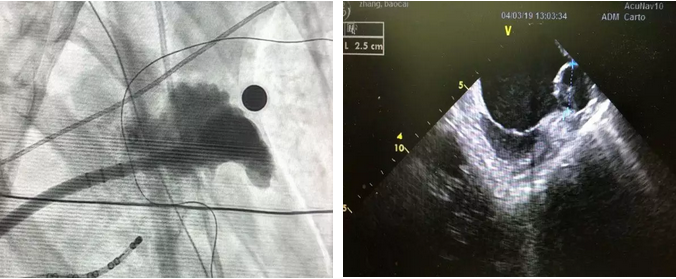

术中造影、超声

经造影和ICE指导下测量发现,该患者的左心耳为大开口鸡翅型浅心耳,开口29mm,深度仅仅有20mm,这是几乎不可能完成的封堵术。

经过反复讨论,杨兵教授最终决定,选择33mm的WATCHMAN™左心耳封堵器,经过体外预借深度和释放时“二次”借深度多种高难度手法的结合运用,封堵器一次展开、顺利到位!

杨兵教授分别再次将ICE导管放置在右房和右室流出道进行封堵器的评估:牵拉稳定,完美封堵!